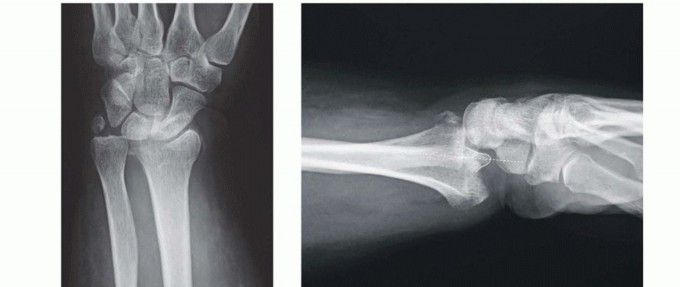

Small fragment volar plate fixation may be indicated for treatment of a volar instability pattern of the volar rim. The fragment must be of adequate size to allow buttressing on the volar surface by the plate ( TECH FIG 5A,B).If volar rim fragmentation is associated with an axial instability pattern, the fragment must be of adequate size and strength to allow angular correction of the dorsiflexion deformity with distal locked screw purchase.An appropriate volar approach is used to expose the volar rim fragment. If a shortened radial column fragment is present, restoring radial length and provisionally holding with a trans-styloid Kirschner wire may simplify reduction by unloading the lunate facet.Reduce the volar rim fragment; this should restore normal carpal alignment.Apply a small fragment volar plate and fix it proximally with cortical bone screws. If needed, secure the distal fragment with standard or locking bone screws ( TECH FIG 5C,D).

VOLAR BUTTRESS PIN FIXATION

TECH FIG 5 • Volar rim fixation with small fragment plate. A,B. Shear fracture of volar rim with volar instability pattern. C,D. Fixation with small fragment plate.